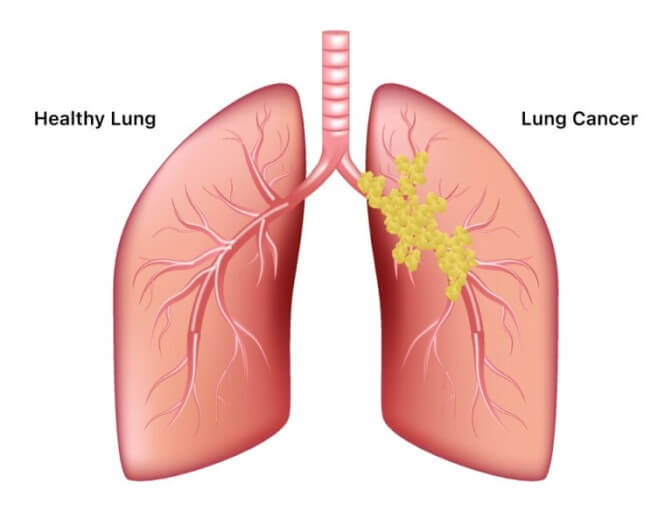

2차성 기흉은 교통사고나 외상 등의 충격으로 인해 폐가 손상될 경우 발생합니다.

만성 폐 질환이나 결핵, 암 등으로 인해 발생할 수도 있고, 유전적 요인으로 인하여 발생할 수도 있습니다.